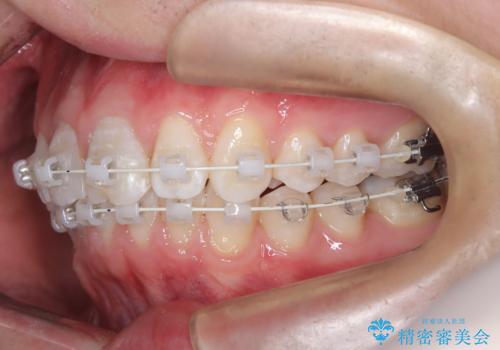

【ワイヤー矯正 11ヵ月で矯正終了!】歯のでこぼこを治したい!

- 矯正装置

- ワイヤー(審美装置)

- 11ヶ月

- 「歯のでこぼこを治したい 1年くらいで矯正を終わらせたい」を主訴に来院された患者様です。

叢生量は多く無く歯の傾斜も標準傾斜だったので歯は抜かずにワイヤー矯正で治療を行いました。

左側は2級傾向が強く臼歯の遠心移動をご提案しましたが、1年以内に矯正を終わらせたいという患者様のご意向で希望されず叢生を改善する矯正となりました。